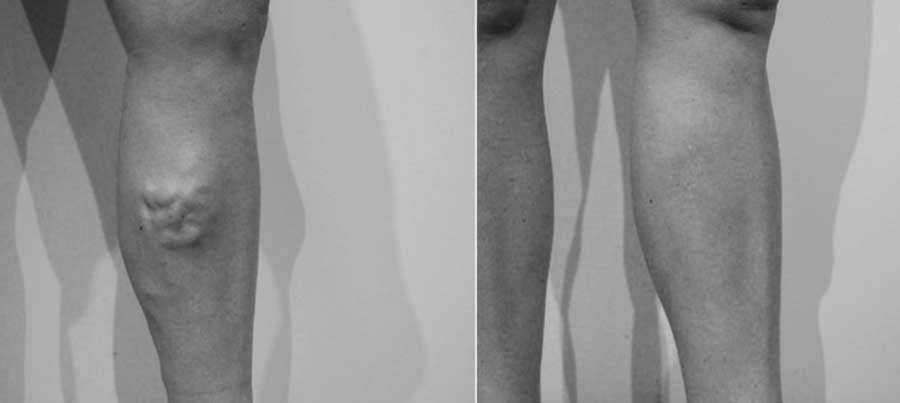

Le laser endoveineux est un traitement de choix dans le traitement des varices.

Les varices plus superficielles seront bien sûr traitées dans le même temps par phlébectomie ou seront sclérosées en consultation dans un second temps.

Cependant ce laser ne s’adresse pas à tous les cas de varices, Le médecin que vous consulterez vous expliquera clairement en fonction de votre état général et des résultats du doppler échographie quel est le meilleur traitement pour vous:

En conclusion, Laser endoveineux ou chirurgie mini invasive ne peuvent pas être opposés ni comparés, chacun a ses indications en fonction de votre état général, et du type de varices.